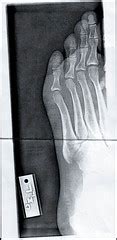

The broken ends of the bone have been shattered into many pieces. Learn vocabulary, terms and more with flashcards, games and other study tools. Choose from 65 different sets of flashcards about compound fracture on quizlet. Starring 3 icons of horror: A compound fracture, or open fracture, breaks the bone, and then the broken pieces of bone pierce the skin. Compound fracture meaning, definition, what is compound fracture: Compound fractures are more serious than simple fractures. A fracture caused by a disease or condition is known as a pathological fracture. There are different causes and types of fractures. It's often the fragment of the bone itself that breaks through the skin and causes the open wound. The average person has two during a lifetime. Bone is broken all the way through. Most often, this wound is caused by a fragment of bone breaking through the skin at the moment of the injury. A compound fracture can be defined as the fracture in the bone that protrudes through the skin resulting in an external wound. Also known as an open fracture, compound fractures occur when there is an open wound or skin tear in the affected area, making the broken bone visible. A break or fracture is detected. Your risk of fracture depends, in part, on your age.